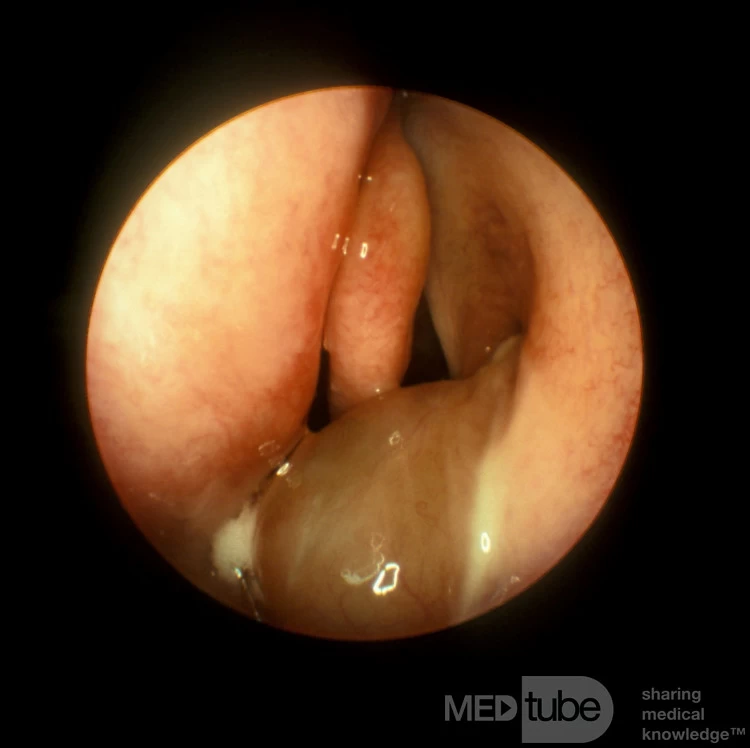

Polyp mũi sau

Polyp antrochoanal này bắt nguồn từ bên trong xoang hàm trên bên trái. Lưu ý cuống của polyp khi nó đi vào khoang mũi thông qua một lỗ thông xoang hàm trên phụ nằm ở thóp mũi trước. Được cung cấp bởi Giáo sư Heinz Stammberger, Đại học Graz, Áo